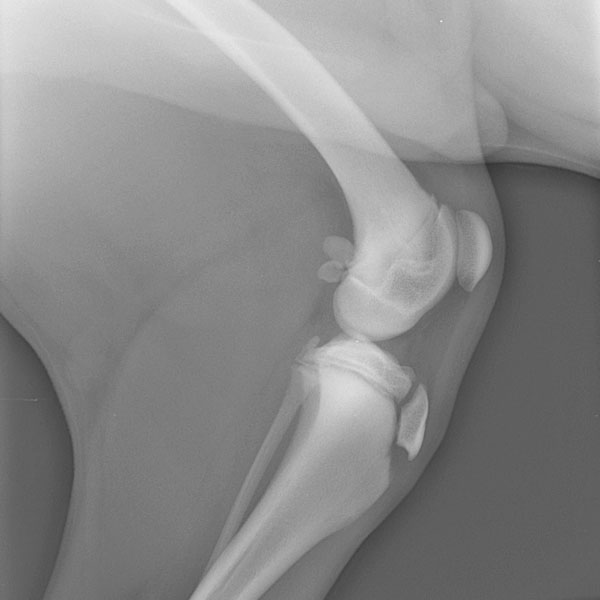

Essentiell ist die Röntgenuntersuchung in der Kleintiermedizin in vielen Bereichen der Skelett- und Weichteildiagnostik. Frakturen und Luxationen, degenerative Gelenkveränderungen, genetisch bedingte angeborene Skelettanomalien können gleichsam wie bestimmte Veränderungen an inneren Organen, Tumore, Flüssigkeitsansammlungen in den Körperhöhlen, Fremdkörper etc. nur durch röntgenologische Abklärung eindeutig erkannt und somit auch bestehende Therapiemöglichkeiten genauer abgeklärt werden.